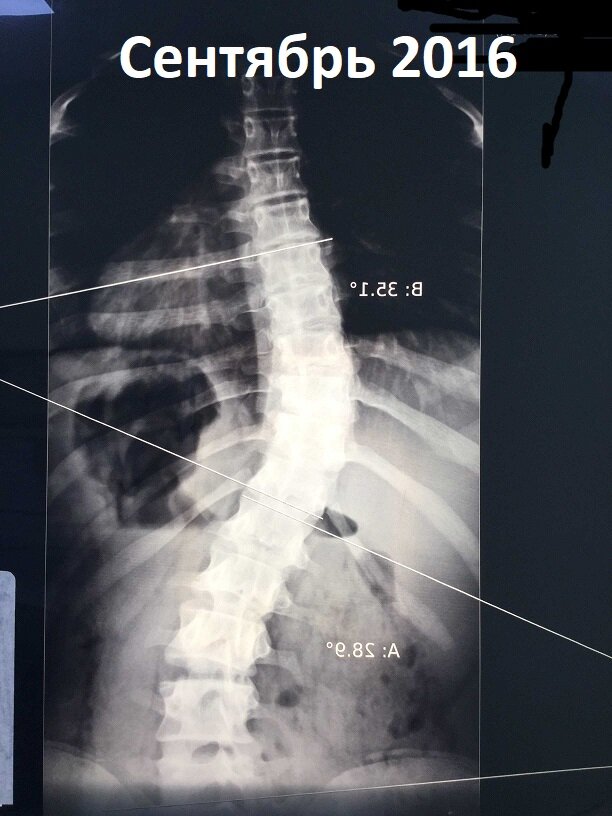

Прошло всего полтора года, а на рентгенах очень хорошо видна положительная динамика.

Девочке 16 лет. Если еще 2 года она будет придерживаться режима, прописанного врачом, у нее есть все шансы войти во взрослую жизнь здоровой и активной.